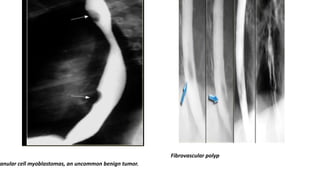

ranular cell myoblastomas, an uncommon benign tumor.

Fibrovascular polyp

ranular cell myoblastomas,an uncommon benign tumor. Fibrovascular polyp